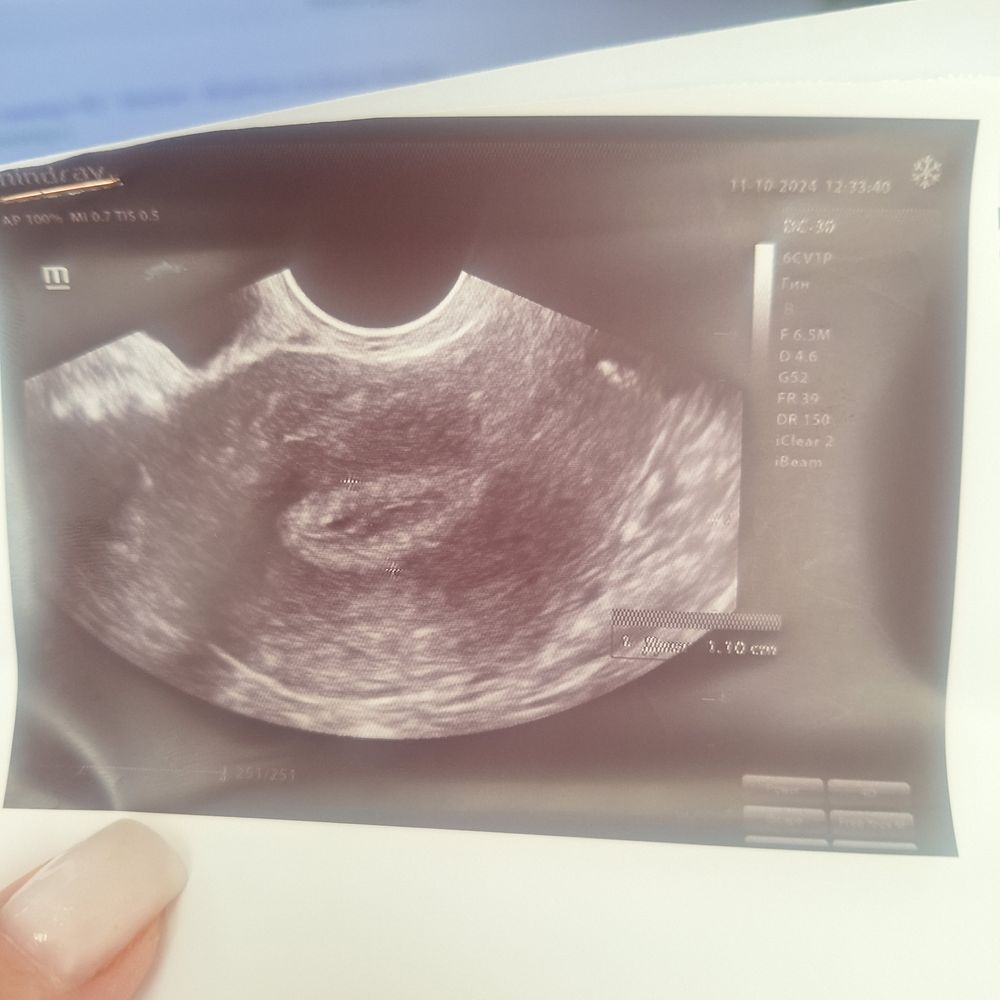

Вышла замуж второй раз,до этого 10 лет прожила с первым мужем,был выкидыш на сроке 12 недель,потом анэмбриония, и вот со вторым мужем планируем беременность уже год,но не получается,начала обследоваться,врач направила на УЗИ,посмотреть эндометрий,и вот врач выдал мне снимок узи,сказал вам ваш врач все скажет,но я когда была беременная у меня такое же УЗИ было,до месячных еще 10 дней(может ли вообще такое быть) и вот вопрос-мне кажется или на узи плодное яйцо??

Как по мне что то странное УЗИ какое-то. Что за ( как будто жидкость в матке) я помню много своих УЗИ но такое, точнее похожее было после чистки, когда кровь в матке оставалась

Сфоткайте заключение, где текстом написано, все измерения и тд. Это не ПЯ, по-моему. Но я не врач 🤷♀️

Ника, там за беременность не слова,просто у меня узи с первой беременностью один в один было)вот надежда теплится,но конечно рано о чем то говорить